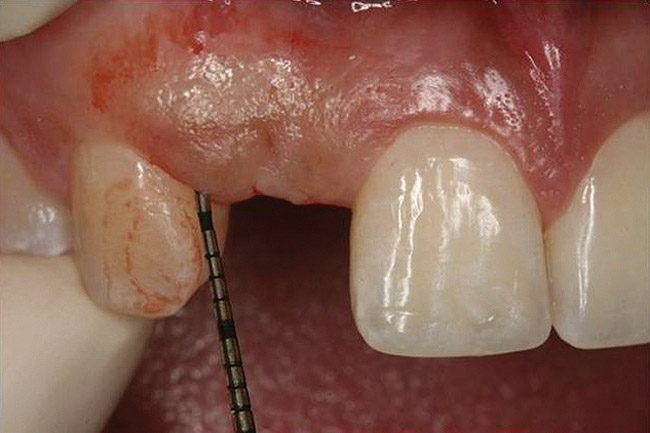

Figure 10  Clinical examination of the bound edentulous space: Measurement of the distal (Fig 10) and mesial (Fig 11) interproximal tissue height using a periodontal probe supplements data obtained from the periapical radiograph. Estimation of the buccal tissue thickness (bone sounding) is performed at the determined location of the gingival zenith using a guide developed from the diagnostic waxing (Fig 12).

Figure 10

Figure 11   Clinical examination of the bound edentulous space: Measurement of the distal (Fig 10) and mesial (Fig 11) interproximal tissue height using a periodontal probe supplements data obtained from the periapical radiograph. Estimation of the buccal tissue thickness (bone sounding) is performed at the determined location of the gingival zenith using a guide developed from the diagnostic waxing (Fig 12).

Figure 11